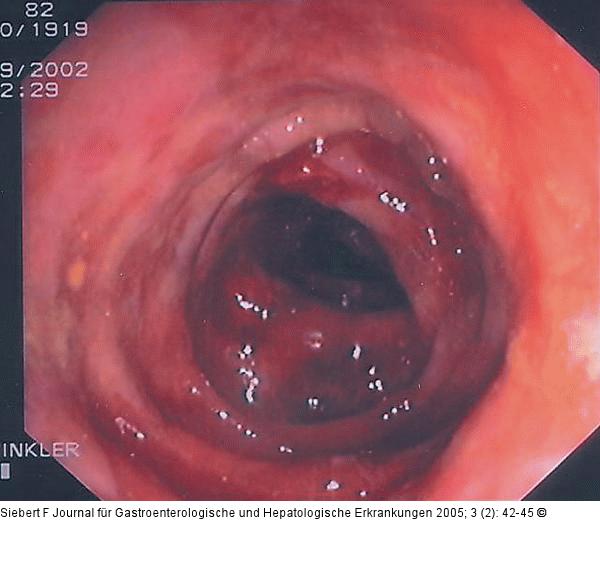

Abbildung 7a-c: Kolon-Ischämie - Differentialdiagnosen Differentialdiagnose Infektiöse Colitis - Strahlencolitis - Colitis ulcerosa (von oben nach unten) |

Abbildung 7c

Abbildung 7a-c: Kolon-Ischämie - Differentialdiagnosen

Differentialdiagnose Infektiöse Colitis - Strahlencolitis - Colitis ulcerosa (von oben nach unten) |